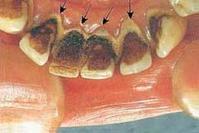

牙结石又称牙石,它是由食物残渣、坏死脱落的口腔上皮细胞唾液中的矿物质钙化后附着在牙齿表面而形成的。并呈现出黄色、棕色、或者黑色。

牙结石通常存在于唾液腺开口处的牙齿表面(例如:下颚前牙的舌侧表面,上颚后牙的颊侧表面)和牙齿的颈部,以及口腔粘膜运动不到的牙齿表面等处。牙结石开始时是软软的,会因逐渐的钙化而变硬。它是由75%的磷酸钙,15-25%的水、有机物、磷酸锰、矿酸钙及微量的钾、钠、铁所构成。并呈现出黄色、棕色、或者黑色。通俗地说:“牙结石即牙垢”,是附着在牙面上的矿化的菌斑和其他沉积物的总称。

口腔科日常门诊中,常有老年人因牙龈出血或口臭来就诊。经检查,确定发生这些症状的原因主要是牙结石。大部老年人都有程度不同的牙结石。牙结石是附着在牙齿表面的硬性斑块,其外形似黄色干石灰块,较坚硬,易使牙龈出血。牙结石大多位于不易清洁的牙面上,如下前牙舌面、上磨牙颊面。引起牙结石的原因很多,如炎症、损伤、不良卫生习惯、个体差异(唾液PH值高者易发生牙结石)等。